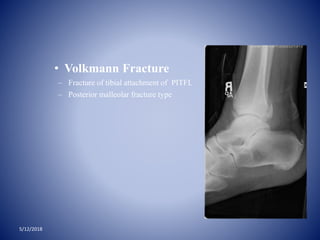

• Volkmann Fracture

– Fracture of tibial attachment of PITFL

– Posterior malleolar fracture type